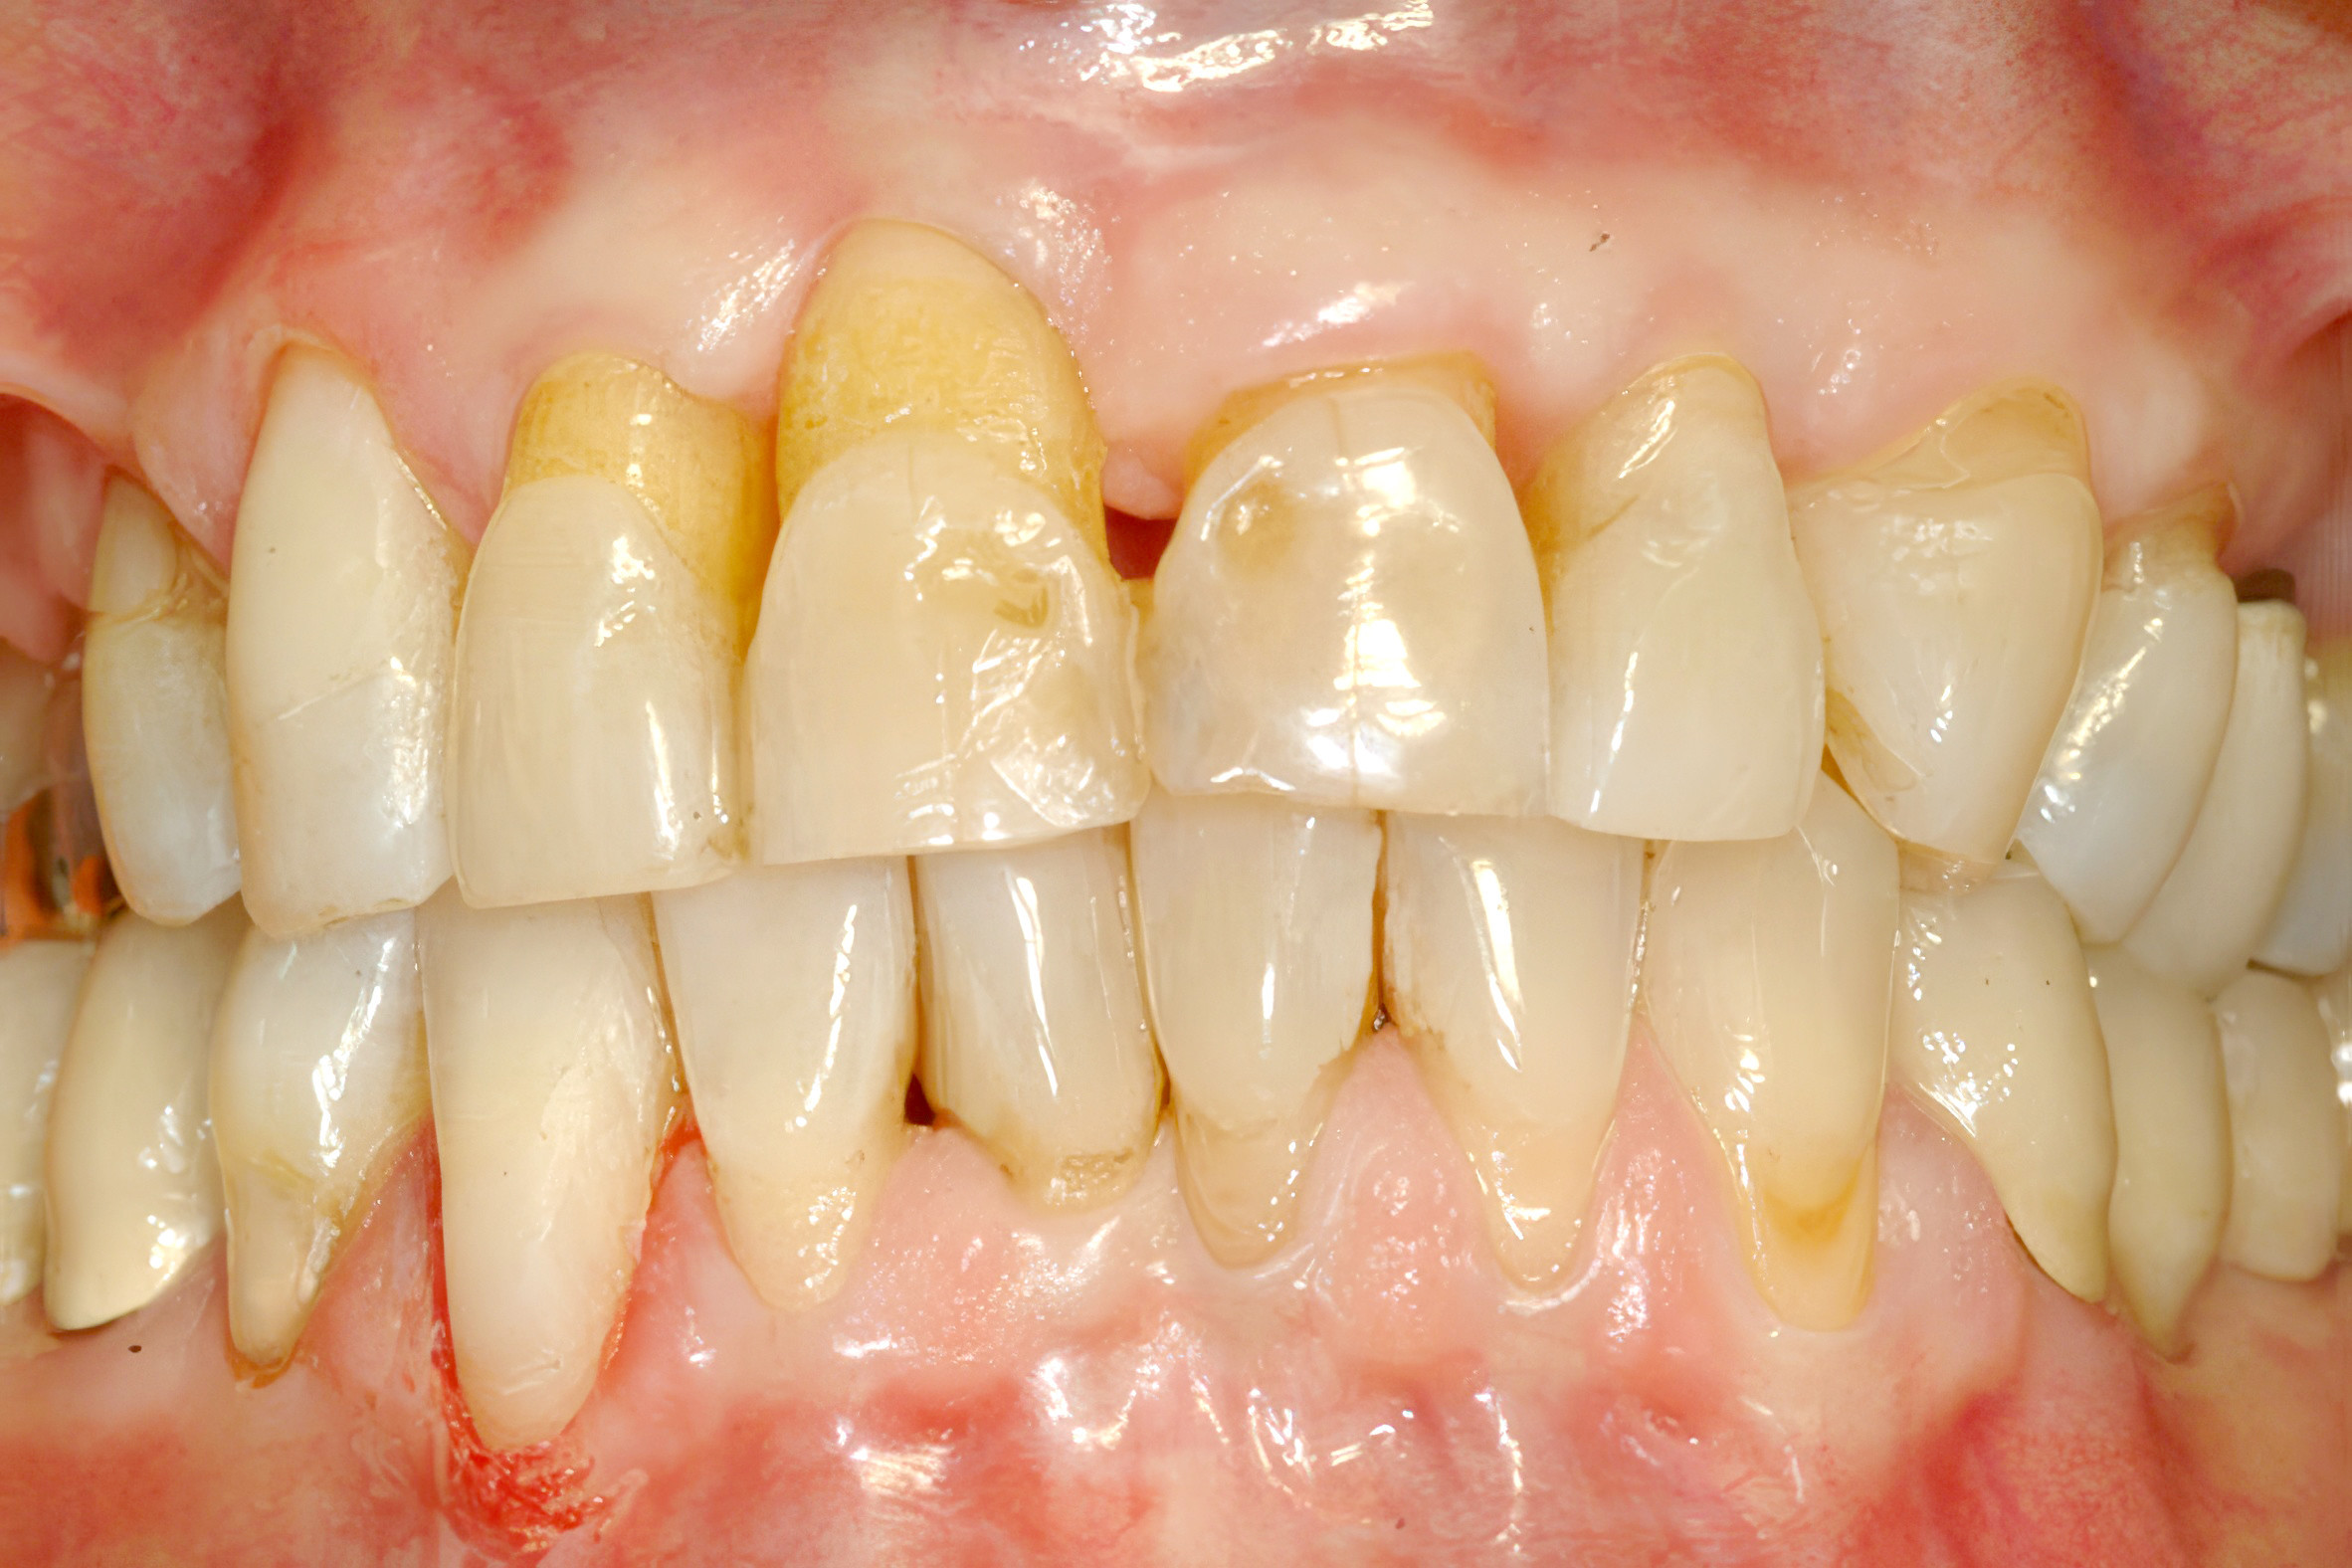

Freiliegende Wurzeloberflächen bei einer 50-jährigen Patientin. Deutliche Rezessionen mit exponierten Zahnwurzelanteilen. © Prof. Dr. Mozhgan Bizhang

Die Erscheinungsformen der Wurzelkaries sind äußerst variabel und reichen von flächenhaften, stark erweichten Läsionen bis hin zu klar abgegrenzten, dunkel verfärbten und harten Läsionen. Diese Läsionen können sowohl an gut zugänglichen Stellen wie den vestibulären Flächen als auch an schwer zugänglichen Bereichen wie im Approximalbereich oder subgingival auftreten. Eine rein morphologische Betrachtung wird jedoch dem dynamischen Charakter der Kariesentstehung nicht gerecht. Nyvad und Fejerskov schlugen daher eine Unterscheidung zwischen aktiver und inaktiver Wurzelkaries vor:9

• Aktive Wurzelkaries: Diese Läsionen erscheinen gelb bis hellbraun und weisen eine weiche, lederartige Konsistenz auf. Häufig sind sie noch von Biofilm bedeckt, was auf eine fortschreitende Kariesentwicklung hindeutet.

• Inaktive Wurzelkaries: Diese Läsionen sind dunkelbraun bis schwarz und besitzen eine normalharte Dentinoberfläche. Dies deutet darauf hin, dass die Kariesaktivität gestoppt oder verlangsamt wurde.